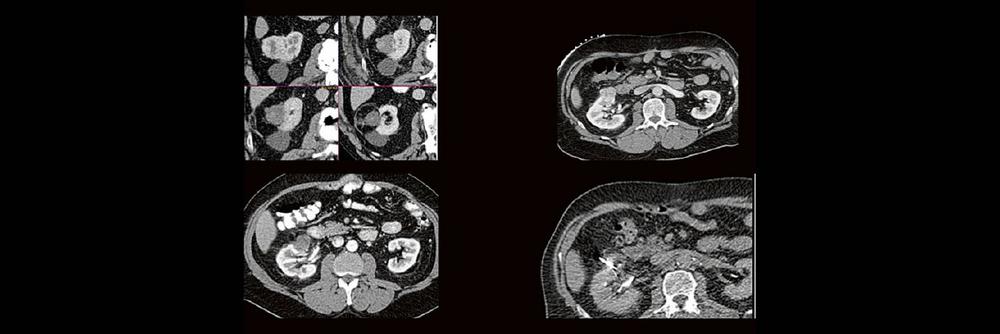

Thermoablation von Nierentumoren (Webinar | Online)

Dr. med. Sascha Alexander Pietruschka Die Anwendung von ablativen Verfahren hat sich in der klinischen Praxis etabliert. Nierentumoren bieten sich für den Einsatz von RFA und Mikrowelle an. Im Dietrich Bonhoeffer Klinikum Neubrandenburg blicken wir auf 15 Jahre Erfahrung mit mehr als 100 RFA/Mikrowellenablationen von Nierentumoren zurück. Im Vortrag werden die eigenen Erfahrungen und Ergebnisse vorgestellt. Dabei wird auf die Indikationsstellung, Vorbereitung, Durchführung, Nachuntersuchungsintervall, Komplikationen und Erfolgsrate eingegangen. ENDLICH ERKANNT – PRAXISRELEVANTE CT ANATOMIE DES ABDOMEN Professor Dr. med. Johannes Weßling Back to the roots! Gute Kenntnisse der Anatomie sind der Schlüssel zur guten Planung, Durchführung und richtigen Diagnosestellung im CT des Abdomens. Lernen sie unverkrampft schnelle Orientierungspunkte für den…